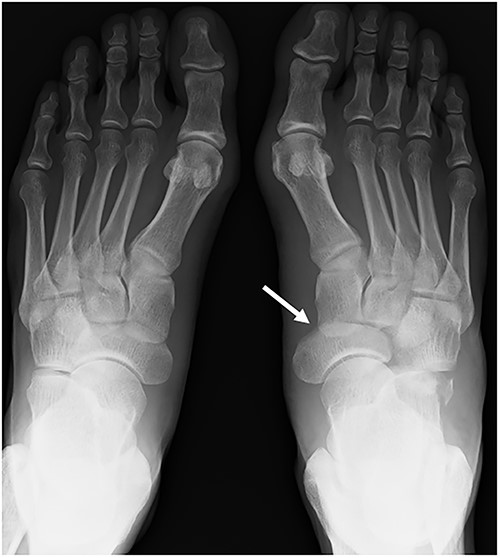

A plain radiograph shows lateral dislocation of the naviculocuneiform and calcaneocuboid joints of the right foot (arrow). The difference between the two sides is obvious.